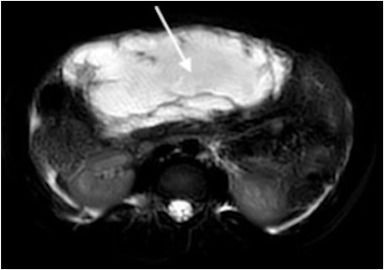

FOAMed Case: Pregnant Woman W/ Intermittent Abdominal Pain

✍️ A woman at 12 weeks gestation w/ history of fibroids presented w/ pain & 2 days of vomiting.

✍️ Physical exam showed diffuse tenderness w/o peritoneal signs.

Learn more via the link ⬇️

🔗 https://bit.ly/4rhexIs

FOAMed Case: Older Man With Abdominal Pain

✍️ An 86-year-old man with history of aortic valve replacement had pain & vomiting after a procedure for cholangitis

✍️ Blood tests showed leukocytosis w/ a normal C-reactive protein.

🔗 below for more on this case!

https://bit.ly/47Qhw35

Older Man With Abdominal Pain

An 86-year-old man with a history of aortic valve replacement presented to the emergency department with right upper quadrant pain and vomiting 3 weeks after undergoing an endoscopic retrograde cholangiopancreatography with stent placement for cholangit...